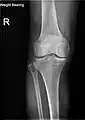

X-ray

Knee X-ray

Knee X-ray (weight bearing)

Knee X-ray (weight bearing, flexion)